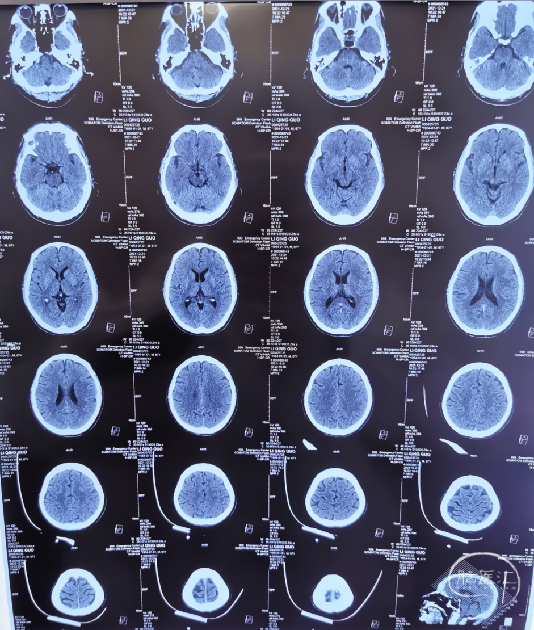

2021-12-21 头颅CT、胸部CT:

1、头颅CT未见明显异常,请结合MRI检查。

急诊头颅CT:未见明显新发梗塞(2021-12-21)

术后第二核磁(2021-12-23):左侧额叶、顶叶、颞叶、岛叶脑梗塞(急性-亚急性)